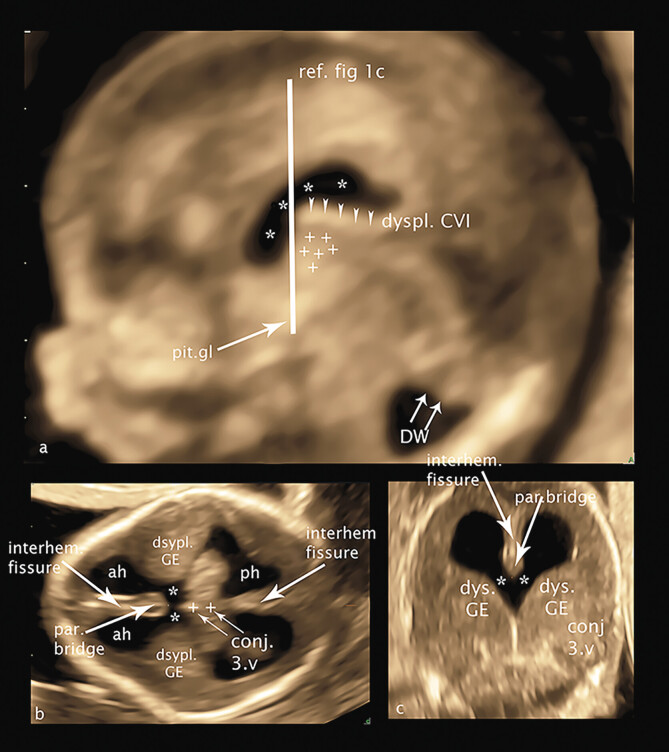

目的探讨高危妊娠冠臀长度为45 ~ 84 mm胎儿的幕上结构——未来透明隔腔、间腔、第三脑室、神经节隆起和丘脑/下丘脑的超声异常。材料和方法本研究回顾性分析了64例胎儿经阴道记录的胎儿脑3D体积,这些胎儿的母亲在GW 12-14期间因胎儿的有机和/或遗传变化向我们的门诊就诊。在这项研究中,我们选择了具有最佳超声质量的胎儿脑3D体积块的胎儿,以便对幕上脑结构进行详细分析和测量,并将结果与遗传分析结果、妊娠后期超声控制和胎儿结局相关联。结果在44例遗传改变胎儿和20例综合征改变胎儿中,27例胎儿发现脑结构改变,并将脑结构与近期发表的妊娠早期12-14周脑结构进行对比分析,首次揭示了早期病理性脑发育的新细节——迁移障碍、轻度前脑畸形(大叶畸形、MIH)、胼胝体发育不全。结论经阴道三维超声可通过直接超声病理分析和病理结果可视化,高质量地检测和分析GW 12-14脑幕上缺损。

Purpose   To detect sonographic abnormalities of the supratentorial structures of the brain - future cavum septum pellucidum, cavum velum interpositum, third ventricle, ganglionic eminence and thalamus/hypothalamus - in fetuses with a crown-rump length of 45-84 mm in high-risk pregnancies. Materials and Methods   This study presents the retrospective analysis of transvaginally recorded 3D volumes of the fetal brain of 64 fetuses whose mothers consulted our ambulatory department for fetomaternal medicine for organic and/or genetic changes of their fetuses at GW 12-14. For this study we selected fetuses with 3D volume blocks of the fetal brain at best sonographic quality enabling detailed analysis and measurement of the supratentorial brain structures to correlate the results with the results of genetic analysis, ultrasound controls in later weeks of pregnancy, and fetal outcome. Results   Of 44 fetuses with genetic changes and 20 fetuses with syndromic changes, structural brain changes were found in 27 fetuses, analyzed by correlating the brain structures with the recently published structures of the brain at gestational week 12-14 in early pregnancy, presenting new details of early pathological brain development - migration disorders, milder variants of holoprosencephaly (lobar, MIH), corpus callosum agenesis, for the first time in early pregnancy. Conclusion   Supratentorial defects of the brain can be detected and analyzed in GW 12-14 in detail by direct analysis of sonopathology and visualization of pathological measurements using transvaginal 3D sonography in high quality.